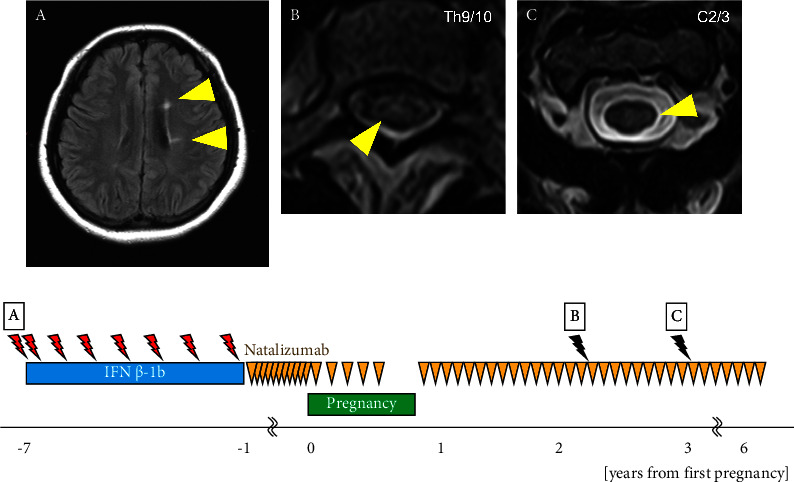

Interferon β and glatiramer acetate are the disease-modifying drugs (DMDs) considered relatively safe for use in pregnant women with multiple sclerosis (MS); however, the safety profile of dimethyl fumarate (DMF) and natalizumab (NTZ) in this population remains inconclusive. Here, we present four cases of pregnant women with MS who were treated with DMF and NTZ (n = 2 patients, each) during their pregnancy and discuss our observations with the use of these drugs and the clinical courses of the patients. We retrospectively examined relapse of MS during pregnancy and after delivery; duration of exposure to DMDs; maternal, fetal, and neonatal adverse events; breastfeeding; and timing of resumption of DMDs. The two patients treated with DMF discontinued treatment 5 or 6 weeks after the discovery of pregnancy. DMF was resumed 1 week postpartum, and mixed breastfeeding was initiated. Brain magnetic resonance imaging in one patient 9 months after delivery revealed a new lesion; however, it was not classified as a clinical relapse. In two patients treated with NTZ, the dosing interval was extended to 6 weeks after the discovery of pregnancy. One patient discontinued NTZ at 30 weeks and the other at 25 weeks of gestation, as a slight restriction in fetal growth was observed owing to hyperemesis gravidarum. Both patients opted for formula feeding, and no relapse was observed within 1 year postpartum. Additionally, no abnormalities were observed in any of the patients during the perinatal period, and their development was normal. Investigation of drug safety in pregnant and parturient women primarily relies on registries, postmarketing surveillance, and case reports due to ethical limitations on conducting randomized controlled trials. Our findings demonstrated that DMF and NTZ were not contraindicated during pregnancy or the perinatal period in women with MS; nevertheless, vigilant monitoring is essential to ensure the safety of these drugs.